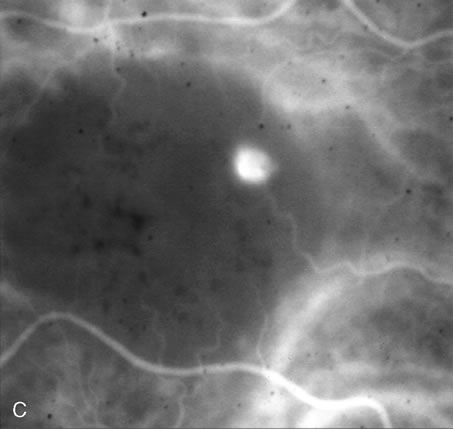

Fig. 5. A. Clinical photograph of a large, crescent-shaped rip of the retinal pigment epithelium (RPE) in the temporal macula. B. Early-phase fluorescein angiography study demonstrates the presence of a window defect corresponding to the RPE rip, which exposes the choroidal vasculature. Where the RPE is redundant in the central macula there is blockage of the normal choriocapillaris fluorescence. C. Late-phase angiogram reveals intense hyperfluorescence seen through the RPE defect.